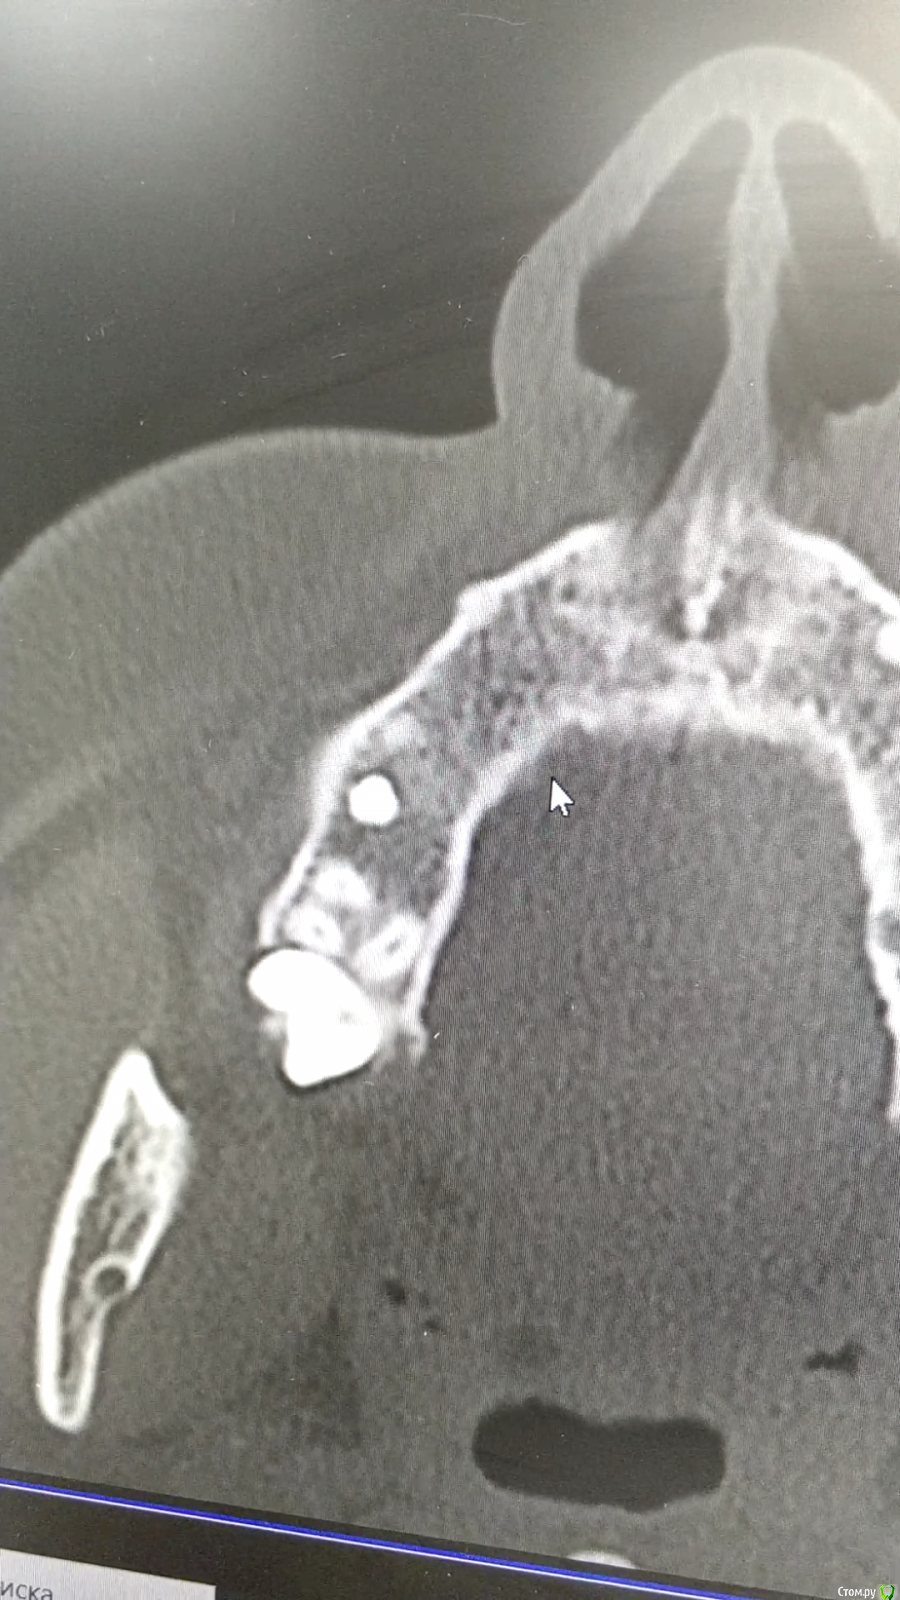

Raystom Опубликовано 10 октября, 2020 Автор Поделиться Опубликовано 10 октября, 2020 Пришла сегодня на прием, неприятные ощущения сохранены, принесла КТ от Лора и вот что там есть Ссылка на комментарий

Raystom Опубликовано 10 октября, 2020 Автор Поделиться Опубликовано 10 октября, 2020 Переимплантит и выкручивать? Ссылка на комментарий

Raystom Опубликовано 10 октября, 2020 Автор Поделиться Опубликовано 10 октября, 2020 Внешне никаких проявлений, пальпация с нёбной стороны слабоболезнена Ссылка на комментарий

kramer Опубликовано 10 октября, 2020 Поделиться Опубликовано 10 октября, 2020 А состояние пазухи по КТ? Ссылка на комментарий

Irouil Опубликовано 10 октября, 2020 Поделиться Опубликовано 10 октября, 2020 Снимки ничего плохого не говорят. Соседние зубы что? Ссылка на комментарий

Raystom Опубликовано 10 октября, 2020 Автор Поделиться Опубликовано 10 октября, 2020 (изменено) А состояние пазухи по КТ? заключение Лора, с пазухой всё ок и расстояние до пазухи от импланта около 2мм Изменено 10 октября, 2020 пользователем Raystom Ссылка на комментарий

Raystom Опубликовано 10 октября, 2020 Автор Поделиться Опубликовано 10 октября, 2020 (изменено) Снимки ничего плохого не говорят. Соседние зубы что? внешне без проблем, КТ завтра гляну. Неприятные ощущения по ходу носогубной складки снизу-вверх сохранены, говорит, что когда закрывает глаз справа чувствует напряжение. Пальпация с неба слабоболезнена, но не сразу, а через полминуты и проходит через полминуты Изменено 10 октября, 2020 пользователем Raystom Ссылка на комментарий